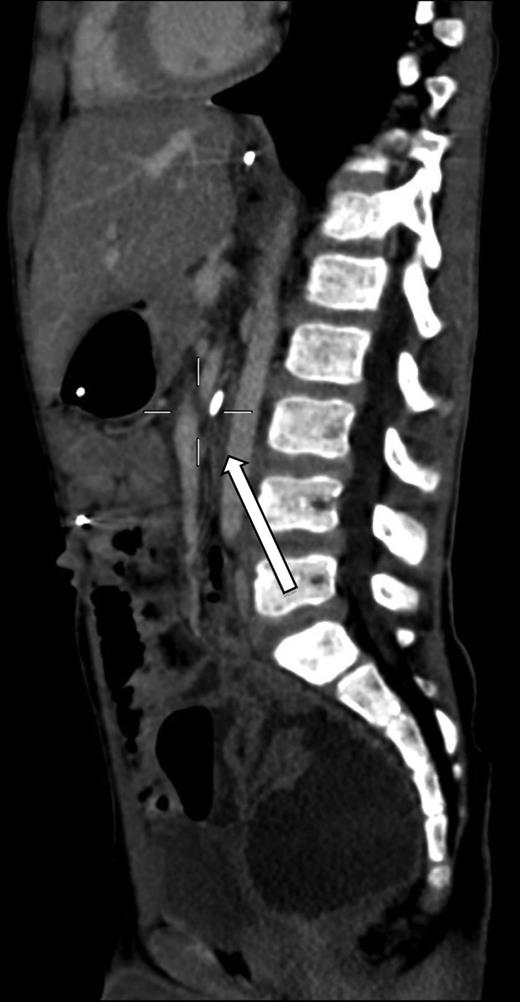

A 7-year-old boy who had been treated at 3 years of age for a subtotal colonic Hirschsprung disease with a Deloyers’ procedure was admitted for persistent bilious vomit associated with recurrent episodes of postprandial abdominal pain and diarrhea. The parents reported a progressive weight loss of 3.5 kg during the last 3 years. The patient was emaciated with severe chronic malnutrition; the weight and the length were 15.19 kg and 113 cm [body mass index (BMI): 11.9 kg/m2], both between the third and the fifth percentile, respectively. The clinical abdominal examination was normal. A plain abdominal X-ray showed a distended stomach with paucity of gas in the distal bowel. An abdominal ultrasound confirmed a dilated duodenum without signs of mechanical obstruction of the small bowel and a normal relationship between the superior mesenteric vessels. An upper gastrointestinal contrast study confirmed dilatation of the first and second portions of the duodenum with little progression of contrast medium across the third portion released in left lateral position (Fig. 1). An SMAS was confirmed by a computed tomography (CT) scan that showed a reduction in retroperitoneal preduodenal and mesenteric fat and compression of the third duodenum by the superior mesenteric artery with an acute 13° angle and a 7.5 mm distance from the aorta (Fig. 2). A gastrointestinal endoscopy confirmed the dilatation of the duodenum with an inflammatory mucosa and a normal jejunum. Gastric and duodenal biopsies were performed and a nasojejunal tube was guided through the duodenum to the Treitz to start enteral feeding (Fig. 3).

The SMAS results from vascular compression of the third part of the duodenum due to the reduction in the acute angle and distance between the superior mesenteric artery and the abdominal aorta. Several predisposing conditions for SMAS have been identified, including abdominal surgical procedures and dietary disorders with a significant weight loss [1–3]. In our patient, the etiology of SMAS may be related to two causes: the Deloyers' procedure employed for the treatment of total Hirschsprung disease, and undiagnosed celiac disease with associated malabsorption and weight loss. The Deloyers’ procedure allows to obtain a colorectal or coloanal anastomosis. After a left colectomy extended to the transverse colon and rectum, the right colon is rotated in a craniocaudal and a counter clockwise direction to avoid compression of the terminal ileum, and it is pulled down into the pelvis. Similar to surgical procedures of the ileoanal pouch performed in adult patients, the Deloyers' maneuver may cause traction in small bowel mesentery changing the relationship between the vascular structures forming the aortomesenteric angle [4]. This anatomical modification may have reduced the aortomesenteric angle making our patient susceptible to SMAS [5, 6]. The progressive weight loss related to malabsorption associated with celiac disease may have led to depletion of the retroperitoneal preduodenal and mesenteric fat with a further decrease of the aortomesenteric angle and distance, worsening the duodenal obstruction. SMAS diagnosis was derived from the upper gastrointestinal radiography associated with the CT scan that demonstrated the location of the duodenal obstruction between the aorta and the superior mesenteric artery with an acute aortomesenteric angle and a reduced aortomesenteric distance measuring 13° and 7.5 mm, respectively. In the adult population, the aortomesenteric angle and distance range from 20° to 70° and from 10 to 34 mm, respectively [7]. The normal value in children is unknown. Upper gastrointestinal endoscopy, as used in this patient, may be a useful diagnostic and therapeutic tool to rule out associated pathologies that may create a predisposition for the development of SMAS, and the placement of a jejunal tube to bypass the obstruction is useful to administer hypercaloric enteral feeding avoiding parenteral nutrition [8]. In conclusion, as reported in adults after ileoanal pouch anastomosis, SMAS should be considered as the cause of upper gastrointestinal obstruction in children treated by a Deloyers' procedure or ileoanal anastomosis. Close attention must be given during preparation of the mesentery avoiding any possible source of traction and employing, if necessary, the ruses for mesenteric lengthening in adult patients [9]. It is always important to follow the clinical course of operated children for they can present symptoms and signs not related to surgery as in this reported case. According to the most recent guidelines by ESPGHAN on celiac disease, our patient was able to meet the criteria outlined to avoid duodenal biopsy with serum levels of IgA anti-TG2 >10 falling within the normal value with a strong suspected clinical picture originally interpreted as a sequela of the previous surgery [10]. In this patient, we were forced to take a journey back from duodenal biopsies to serology IgA anti-TG2 when the clinical findings already led to diagnosis. This process that led to severe malnutrition with worsening of SMAS, to several radiological and invasive procedures and to several hospitalizations could have been avoided. Only a close medical and surgical follow-up can avoid an underestimation of early clinical signs unrelated to surgery.